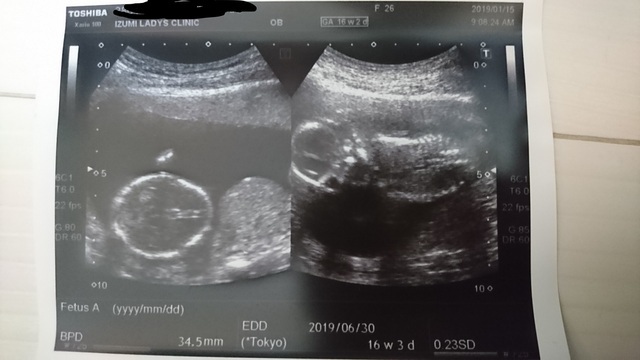

16週3日(16w3d・性別不明)|ま211 さん(27歳)

エコー写真撮影時のエピソード:

だんだんと赤ちゃんらしくなりエコー中よく手を動かしています。よく顔を触ってるから照れ屋さんかな?

でもお腹が張って切迫流産で入院になったけど、赤ちゃんはすくすく育ってて安心!しばらく絶対安静頑張ります!